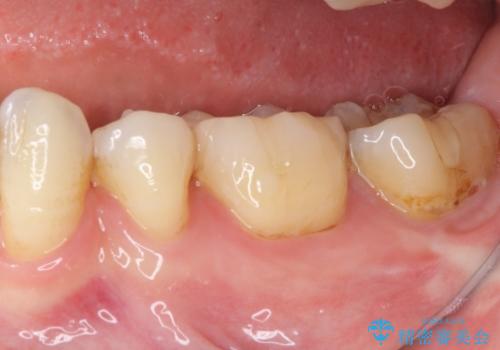

- 下の奥歯に虫歯ができてしまったとのことで来院された患者様です。

他にも気になる歯はありましたが、急を要する1歯のみをセラミックインレーにて修復治療を行うこととしました。

奥歯において、隣の歯と接触する部分に虫歯が及んでしまった場合、その場で充填を行う処置(コンポジットレジン修復)ですと、充填の縁に大きなギャップが生じてしまう可能性が高く、2次的な虫歯を引き起こすことになります。

また、処置した歯の後方にある歯は保険診療で使用するレジンインレーが装着されていますが、縁に虫歯が出来はじめていることが分かります。